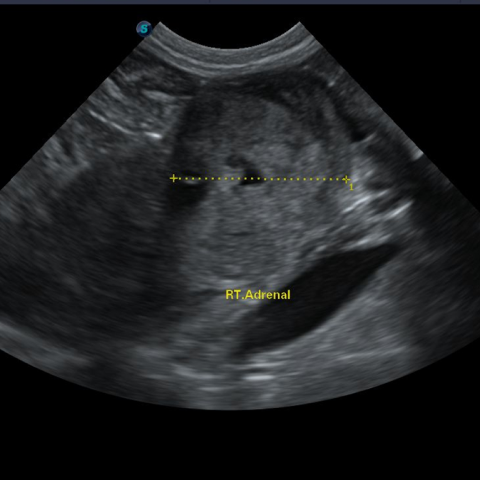

¿ìÃø ºÎ½Å ºñ´ë